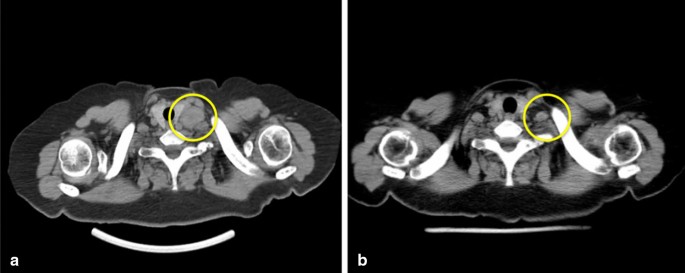

Gastroscopy performed 3 years ago revealed an obvious gastric mass around the gastric antrum which proved to be poorly differentiated adenocarcinoma by cytologic evaluation. The chest CT at the same time showed obvious enlargement of supraclavicular lymph nodes. Afterwards, the patient received 6-course chemotherapy of SOX (S-1 and oxaliplatin) regimen. Contrast-enhanced computed tomography on admission this time revealed the previously enlarged cervical lymph nodes significantly shrank (Fig. 1) and gastroscopy on admission also revealed the previous obvious gastric mass at the gastric antrum had shrank into an ulcer scar at the lesser curvature. Positron emission tomography/computed tomography (PET/CT) showed previous multiple lymph nodes with increased metabolism at the lesser curvature of stomach, para- abdominal aorta and bilateral supraclavicular fossa were no longer obvious on admission (Fig. 2). All of these evidences demonstrated that the patient’s gastric adenocarcinoma achieved complete response after neoadjuvant chemotherapy.